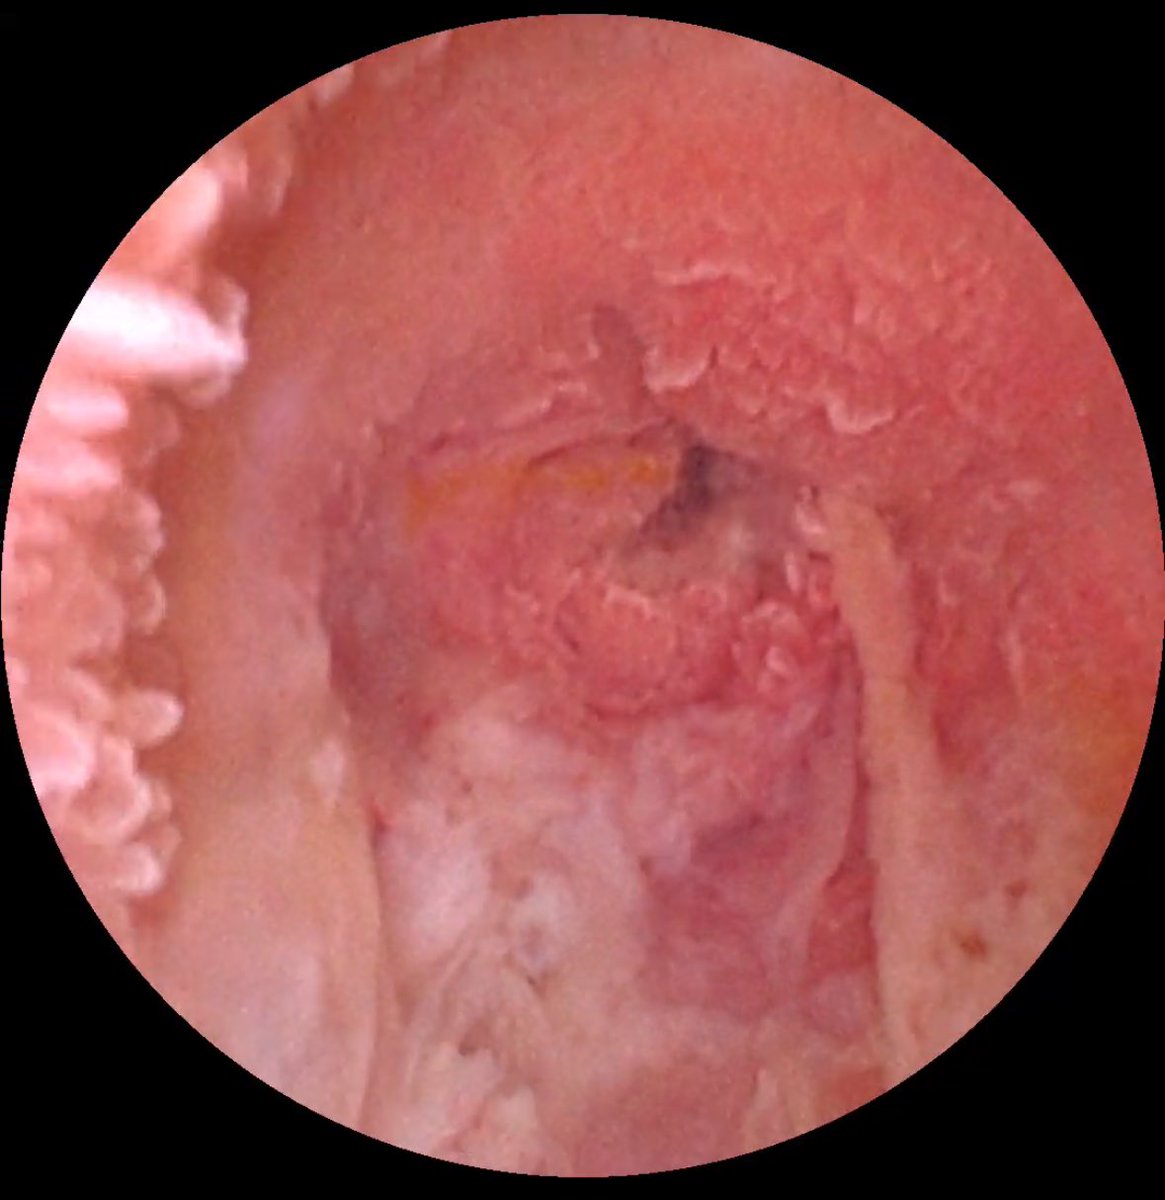

في إنجاز طبي يعد الأول من نوعه في المنطقة الشرقية، تم بنجاح إجراء منظار للقنوات الصفراوية في الكبد عن طريق الجلد، مع تنظيف القنوات الصفراوية وأخذ عينة، وذلك في وحدة الأشعة التداخلية بمستشفى الملك فهد الجامعي.

أتوجه بجزيل الشكر والتقدير إلى إدارة قسم الأشعة التشخيصية وإدارة مستشفى الملك فهد الجامعي وإدارة جامعة الإمام عبد الرحمن بن فيصل على دعمهم المستمر وتوفير الإمكانيات اللازمة لإنجاز مثل هذه الإجراءات المتقدمة، مما يعزز من جودة الرعاية الصحية المقدمة للمرضى.

كما أود أن أعبر عن امتناني العميق للفريق الطبي والفني في وحدة الأشعة التداخلية على جهودهم المتميزة وتفانيهم في تحقيق هذا النجاح.

ولا يفوتني أن أشكر الزملاء الأعزاء من مختلف التخصصات على تعاونهم المثمر ودعمهم خلال هذا الإجراء:

افتتح عميد كلية الطب د.بندر الجفن والمدير التنفيذي للشؤون الصحية في #المدينة_الطبية بـ #جامعة_الملك_سعود د. عبدالعزيز الثنيان ورئيس قسم الاشعة والتصوير الطبي د.نوران ملا ورشة عمل علاج أمراض القنوات الصفراوية باستخدام تقنية المناظير عن طريق الجلد بمشاركة نخبة من الأطباء المتخصصين في مجال الأشعة التداخلية، تم من خلالها طرح أبرز المستجدات والاكتشافات والتجارب في علم الأشعة التداخلية والمناظير، حيث تعتبر هذه الورشة هي الأولى من نوعها على مستوى العالم.

وكانت ورشة العمل تدار بالاستعانة بخبرات نخبة من الاستشاريين تضم د. أحمد الأحيدب @alehaideb ، د. بسام الرحيلي @DRSTINGRAY ، د. تركي الفرحان @Turki_fs ، د. سلطان الحربي ، د. عبدالله الجهني @AljohaniMD ، د. علي الجمعة @AljomahAli1 ، د. عمار العتيبي @DrAmmarAlotaibi ، د.يحيى العسيري @YAALSAAS